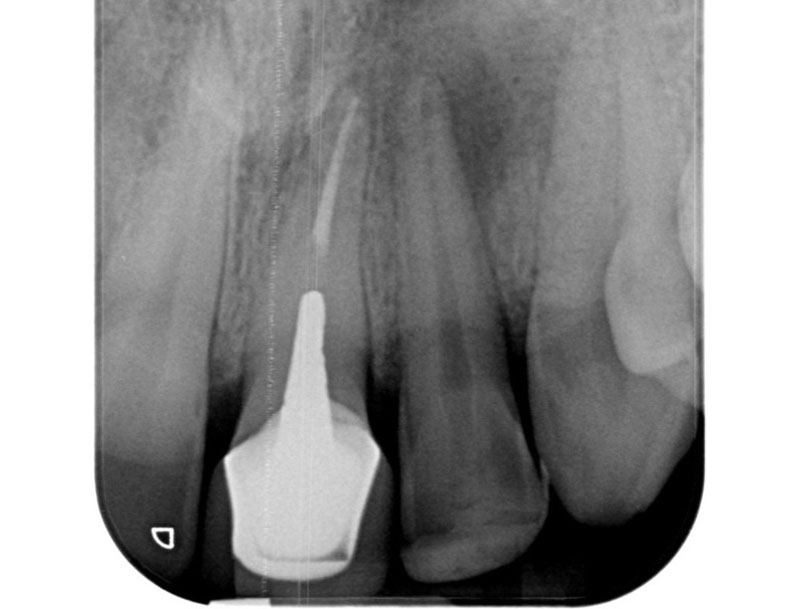

Avant

Après

• Reprise de traitement endodontique : La manœuvre consiste à retourner à l’intérieur des racines d’une dent déjà traitée. Il arrive occasionnellement qu’une nouvelle inflammation se déclare suite à une reprise de carie ou une fracture de la dent, ou si le premier traitement endodontique est incomplet. Après s’être assuré que la dent lésée était conservable, il convient de désinfecter de nouveau le réseau canalaire parfois très complexe. La nouvelle obturation des canaux devra être protégée aussi rapidement que possible pour éviter une éventuelle contamination bactérienne.